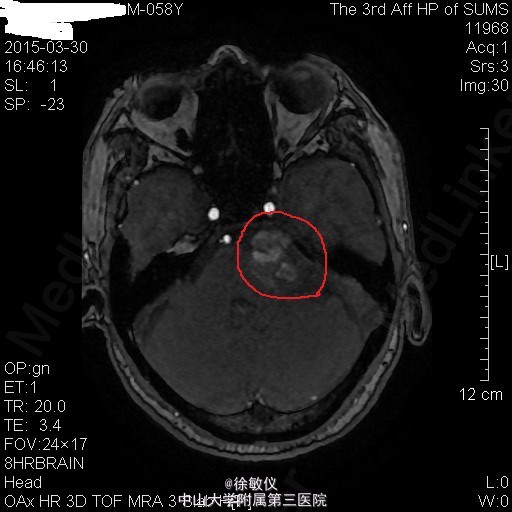

老年患者,主诉:左耳耳鸣、听力下降8年,伴头痛2个月。 现病史:患者8年前始无明显诱因反复出现左耳耳鸣,自诉如鞭炮样鸣响,伴听力进行性下降,无耳道流血流液,可自行缓解。患者曾至当地医院就诊,保守治疗后改善不明显。2个月前始患者出现阵发性全头痛,偶伴头晕、恶心,近2周呕吐胃内容物2次,无发热,无肢体活动异常等不适。于当地医院行头部CT,结果提示:左侧桥小脑角区占位性病变伴出血,听神经瘤(神经鞘瘤)可能性大。患者为进一步治疗来我院。

查体:左耳听力缺失,右耳听力正常。余查体无特殊。 辅查:头部MR:1、左侧桥小脑角区占位病变,考虑为听神经瘤并出血、囊变,病变与左侧听神经、椎动脉关系密切;2、颅脑MRA示脑动脉未见异常。 头部CT:双侧额顶枕叶、半卵圆中心、侧脑室周围、放射冠、基底节区及右侧岛叶多发密度灶,考虑缺血变性灶;颅脑CTA示肿瘤与左侧椎动脉关系密切。